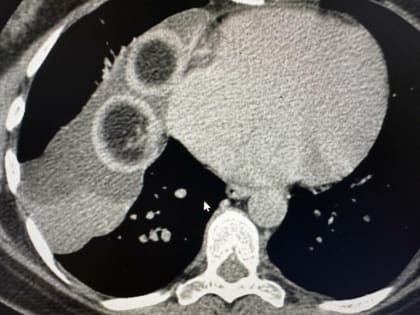

В РКБ удалили кисту с клубками волос, которая выросла рядом с сердцем

Хирурги торакального отделения №1 Республиканской клинической больницы Татарстана удалили пациентке дермоидную кисту с клубками волос внутри.